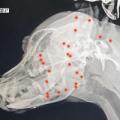

산탄총 파편 70개가 몸 안에…반복되는 동물학대

의료진은 살아있는 것이 기적이라는 표현을 썼는데요. 상처가 아문 상태에서 귀동이를 만난 거지만, 70개 탄환이 박혔을 때 많은 출혈과 함께 굉장히... 최근에는 경남 거제시에서도 끔찍한 일이 있지 않았나요? [기자] 사실 이런 동물 학대 범죄 저희가 한두 번 전해드린 건 아니죠. 언급하신 대로 경남 거제에선...

‘해병대원 비비탄 난사’ 눈 다친 백구, 결국 안구 적출했다

경남 거제시에서 현역 군인 등 남성 3명이 반려견들에게 비비탄을 수백 발 난사해 반려견 한 마리가 숨을 거둔 사건이 공분을 사고 있는 가운데, 피해... 동물보호단체 비글구조네트워크는 지난 2일 공식 소셜미디어(SNS)에 글을 올려 “비비탄 총알에 눈을 맞아 네 번에 걸쳐 치료를 받은 ‘매화’의 눈이 실명돼...

‘비비탄 난사’ 피해견 매화, 결국 안구 적출…“심한 트라우마 시달려...

비비탄 총알에 정통으로 맞은 매화의 눈을 살리기 위해 의료진이 네 번의 마취를 감행하며 치료를 했지만, 결국 실명해 안구 적출 수술을 받을 수밖에... 경찰 등에 따르면 현역 해병대원 2명과 민간인 1명이 지난달 8일 경남 거제시 일운면의 한 식당 마당에 침입해 반려견 4마리를 향해 1시간 넘게 비비탄 총을...

“결국 안구 적출”…해병대원 비비탄 난사에 피해견 트라우마

경상남구 거제시 일운면 한 식당 앞에서 벌어졌다. 현역 해병대원 2명을 포함한 남성 3명이 식당 마당에 침입해 가게에 묶여 있는 강아지 4마리를 향해 비비탄 총알 수백 발을 난사했다. 이로 인해 매화가 중상을 입었으며 7살 잭 러셀 테리어 ‘솜솜이’도 중상을 입고 병원으로 이송됐으나 치료 중 사망했다....